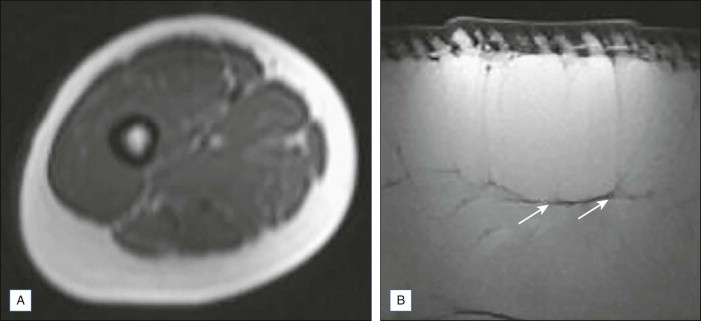

Women with cellulite have a higher percentage of thinner, perpendicularly oriented hypodermal septa than unaffected women and men ( Fig. 12.2 ).

The anatomic hypothesis of cellulite is based on gender-related differences in the structural characteristics of dermal and hypodermal architecture originally detailed by Nurnberger and Muller. They described herniation of fat into the dermis, which is characteristic of female anatomy and which was later confirmed by ultrasound imaging as being low-density regions among denser dermal tissue. Their study revealed that gender related differences are diffuse and not localized to the affected areas. They reported that dermal septa of the affected females are much thinner and more radially oriented than unaffected males, therefore facilitating the extrusion of adipose tissue into reticular dermis. In their study, cellulite-affected and unaffected female subjects both showed an irregular and discontinuous dermal–subcutaneous interface that was characterized by fat protrusion into dermis. The dermoadipose and connective tissue interface was smooth and continuous in male subjects.

Querleux et al. revealed three principal orientations of the septa: perpendicular, parallel, and angulated at about 45° ( Figs 12.3 and 12.4 ). Women with cellulite had a higher percentage of perpendicular septa than unaffected women (p < 0.001) or men (p < 0.01). For the other two directions, according to presence of cellulite, women with cellulite had a smaller percentage of septa parallel to the skin (p < 0.001) and a higher percentage at 45° (p < 0.001).